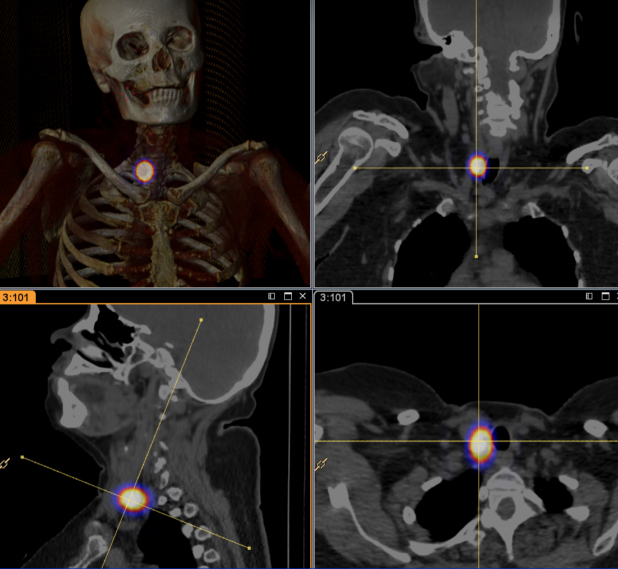

Las figs 2-5 ilustran casos de la serie analizada.

Efectos del AMESPECT

- En 13/17 casos (76%), incrementó un 25% el tamaño detectado de las LLRCT respecto a la ecografía inicial (de 12,6 mm promedio a 16,8 mm.).

- Se reconocieron 22 nuevas lesiones (129% más) sospechosas de LLRCT en 11/17 pacientes (65%), en quienes modificó el plan quirúrgico; 82% de las nuevas lesiones fueron positivas para carcinoma tiroideo.

- En un paciente en que la lesión radiomarcada fue negativa, el AMESPECT localizó dos lesiones más que fueron resecadas y resultaron positivas.

- En otro paciente, AMESPECT determinó la realización adicional de vaciamiento lateral de cuello, con varias adenopatías positivas en la patología.

Como finalmente se resecan 39 lesiones y 34/39 (87%) fueron positivas para LLRCT, la muestra cambia a un n de 39. Si comparamos la sensibilidad y los valores predictivos negativos de la “CRG tradicional” (programada), versus “CRG previo AMESPECT” (resecado), versus patología, se observa lo siguiente:

- La CRG convencional mostró sensibilidad de 47%, VPN de 18.2%.

- La CRG previo AMESPECT mostró sensibilidad de 99.7%, VPN de 88%, en una prevalencia de 88%.